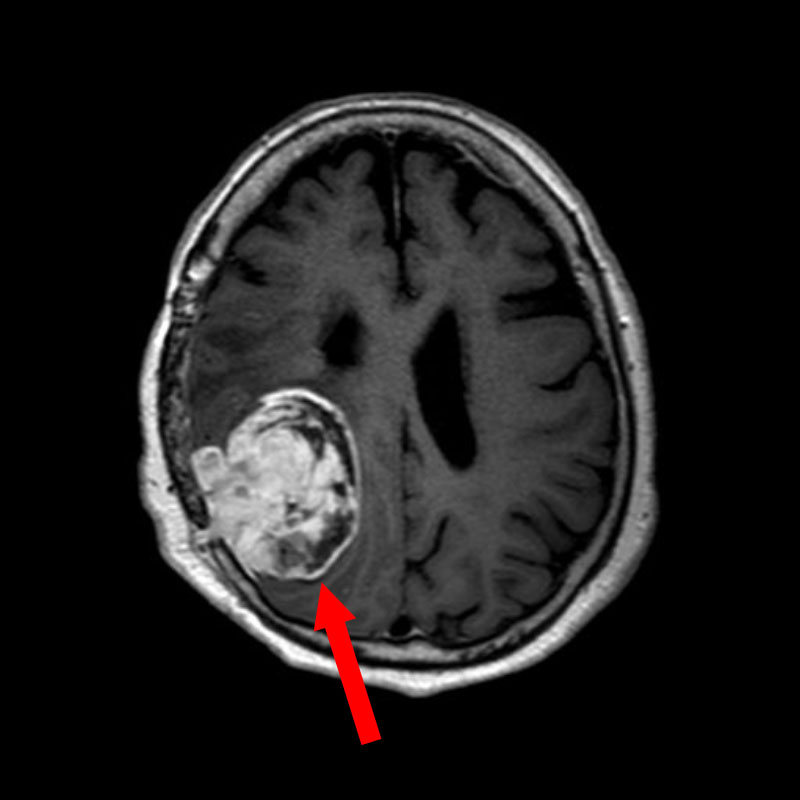

706

'25年12月

80代

右頭頂葉腫瘍

頭蓋内腫瘍摘出術

No.’25_108 手術前1

No.’25_108 手術前2

No.’25_108 摘出 前

No.’25_108  摘出 中

No.’25_108 摘出 後